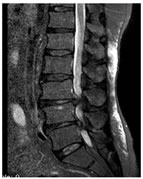

CASE 5

T1W AXIAL IMAGE SHOWING DIFFUSE DISC BULGE, LIGAMENTUM FLAVUM HYPERTROPHY AND BILATERAL FACETAL ARTHROPATHY CAUSING SEVERE THECAL SAC STENOSIS

T2W MID SAGITTAL IMAGE SHOWING MINIMAL RETROLISTHESIS OF L2 OVER L3 AND DISC DEGENERATION AT ALL LUMBER INTERVERTEBRAL LEVELS WITH REDUCED DISC HEIGHT AT FEW LEVELS. THERE IS DISC PROTRUSION NOTED AT L2-3, L3-4, L4-5 LEVELS CAUSING INDENTATION OVER THECAL SAC